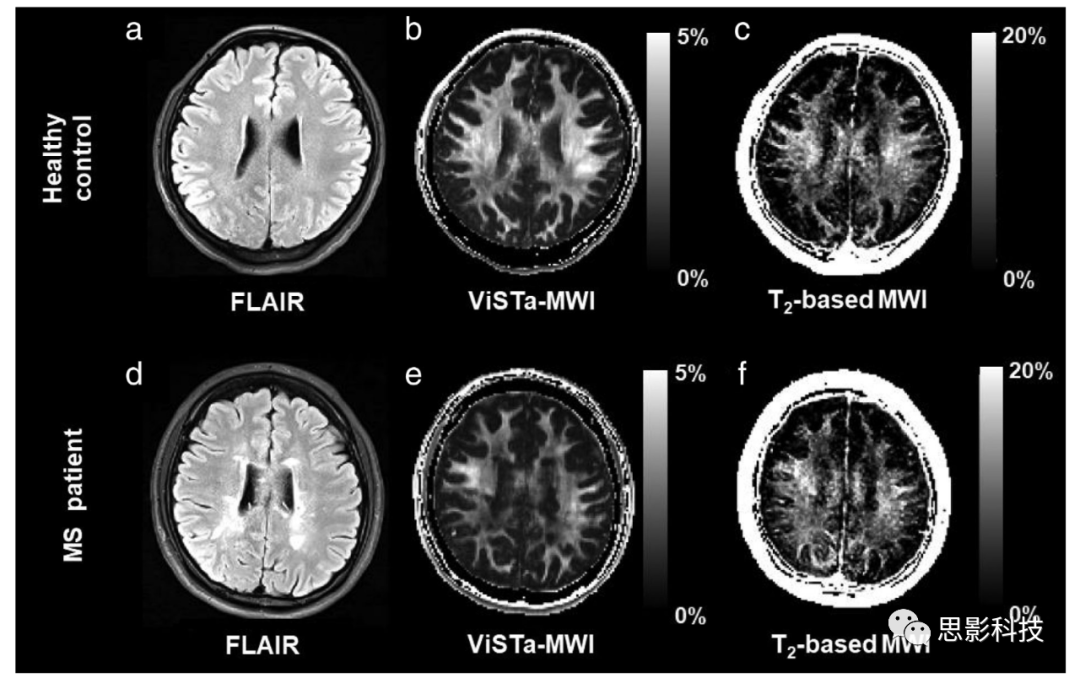

图 4:健康对照(上排)和多发性硬化症患者(下排)的样本图像。

ViSTa-MWI ((b) 和 (e)) 和基于T2的MWI ((c) 和 (f)) 都与FLAIR图像 ((a) 和 (d)) 一起显示。MWI图像显示多发性硬化症患者的MWF减少。

多发性硬化症:多发性硬化症是中枢神经系统的一种炎症性脱髓鞘疾病,髓鞘损伤是其关键的病理学发现。因此,大部分早期的体内MWI研究都是在多发性硬化症患者身上进行的。研究报告显示,与正常外观的白质(NAWM)相比,病变处的整体MWF减少了约50%,尽管病变的状态相当异质。此外,与健康对照组相比,多发性硬化症患者的NAWM的MWF减少了6-37%。除了病变和NAWM,后续研究关注了弥漫性异常白质(DAWM),该病变被定义为具有轻度MRI高信号和边界不清晰的非斑块区域,并报告与多发性硬化症患者的相邻NAWM(正常外观的白质)相比,DAWM(弥漫性异常白质)的MWF减少了23%(体内)或30%(尸体解剖)。所有这些结果都清楚地表明,多发性硬化症大脑的白质中MWF都减少了(参见图4,显示了多发性硬化症的样本MWF图)。除了横断面研究,还有一些研究表明,MWF的纵向分析反映了大脑和脊髓中髓鞘损伤和修复的进行过程。88, 89例如,对接受alemtuzumab治疗的多发性硬化症患者进行的2年纵向MWF评估显示,NAWM中的MWF得到了保留。90这一发现可能为MWI作为特定治疗方案的潜在成像生物标志物提供了实际意义的证据。